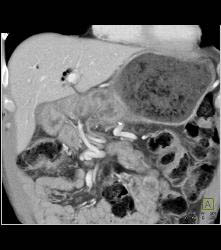

Antral Carcinoma With Peritoneal Tumor Implants